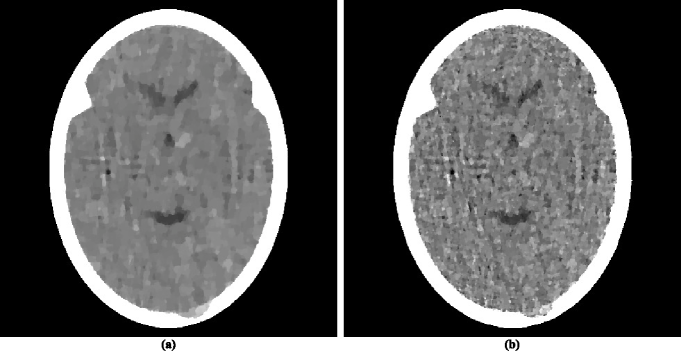

The head phantom that was used for data generation is based on an actual cross-section of the human head. It is described as a collection of geometrical objects (such as ellipses, triangles and segments of circles) whose combination accurately resembles the anatomical features of the actual head cross-section. In addition, the basic phantom contains a large tumor. The actual phantom used was obtained by a random variation of the basic phantom, by incorporating into it local inhomogeneities and small low-contrast tumors at random locations. This phantom is represented by the image in figure 1. That image comprises 485×485485485485\times 485 pixels each of size 0.376 mm by 0.376 mm. The values assigned to the pixels are obtained by an 11×11111111\times 11 sub-sampling of the pixels and averaging the values assigned to the sub-samples by the geometrical objects that are used to describe the anatomical features and the tumors. Those values are approximate linear attenuation coefficients per cm at 60 keV (0.416 for bone, 0.210 for brain, 0.207 for cerebrospinal fluid). The contrast of the small tumors with their background is 0.003 cm-1. In order to clearly see the low-contrast details in the interior of the skull, we use zero (black) to represent the value 0.204 (or anything less) and 255 (white) to represent 0.21675 or anything more).

Refer to caption

Figure 1: (a) A head phantom. (b) Reconstruction of the head phantom from realistically simulated projection data for 360 views using ART with blob basis functions.

For the selected head phantom we generated parallel projection data, in which one view comprises estimates of integrals through the phantom for a set of 693 equally-spaced parallel lines with a spacing of 0.0376 cm between them. (We chose to simulate parallel rather than divergent projection data, since the reconstruction by the method ofSIDK08a (42) with which we wish to compare the superiorization approach were performed for us by the authors ofSIDK08a (42) on parallel data. Even though contemporary CT scanners use divergent projection data, results obtained by the use of parallel projection data are relevant to them, since it is known that the quality of reconstructions from these two modes of data collection are very similar as long as the data generations use similar frequencies of sampling of lines and similar noise characteristics in the estimated integrals for those lines; see, for example, the reconstructions from divergent and parallel projection data in figure 5.15 of HERM09a (55).) In calculating these estimates we take into consideration the effects of photon statistics, detector width and scatter. Details of how we do this exactly can be found in Sections 5.5 and 5.9 of HERM09a (55). Briefly, quantum noise is calculated based on the assumption that approximately 2,000,000 photons enter the head along each ray, detector width is simulated by using 11 sub-rays along each of which the attenuation is calculated independently and then combined at the detector, and 5% of the photons get counted not by the detector for the ray in question but detectors for the neighboring rays. For the experiments in this paper, we did not simulate the poly-energetic nature of the x-ray source. To indicate what can be achieved in clinical CT, we show in figure 1(b) a reconstruction that was made from data comprising of 360 such views with the reconstruction algorithm known as ART with blob basis functions; see(HERM09a, 55, Chapter 11).

There have appeared in the literature some approaches to TV𝑇𝑉TV minimization that seem to indicate a more efficacious performance for CT than the one reported in HERM08a (31). One of these is the Adaptive Steepest Descent Projections Onto Convex Sets (ASD-POCS) algorithm, which is described in detail in the much-cited paper of Sidky and PanSIDK08a (42) and whose use has been since reported in a number of subsequent publications, for example, in SIDK11a (23, 43). We note that ASD-POCS was designed with the aim of producing an exact minimization algorithm, in contrast to our heuristic superiorization approach. Translating equations (6)-(8) of SIDK08a (42) into our terminology, the aim of ASD-POCS is the following: Given an ε+𝜀subscript\varepsilon\in\mathbb{R}_{+}, find an ε𝜀\varepsilon-compatible 𝒙Ω=+J𝒙Ωsuperscriptsubscript𝐽\boldsymbol{x}\in\Omega=\mathbb{R}_{+}^{J} for which TV(𝒙)𝑇𝑉𝒙TV(\boldsymbol{x}) is minimal. (Note that this aim is a special case of the constrained optimization formulation presented in (10).) In order to test ASD-POCS, we generated realistic projection data as described in the previous subsection but for only 60 views at 3 degree increments with the spacing between the lines for which integrals are estimated set at 0.752 mm. Thus the number of rays (and hence the number photons put into the head) in this data set is a twelfth of what it is in the data set used to produce the reconstruction in figure 1(b). A reconstruction from these data was produced for us using ASD-POCS by the authors of SIDK08a (42) (this ensured that it does not suffer due to our misinterpretation of the algorithm or from our inappropriate choices of the free parameters), it is shown in figure 2(a).

Figure 2: Reconstructions using TV𝑇𝑉TV as the optimization criterion from realistically simulated projection data for 60 views using (a) ASD-POCS and (b) superiorization. As compared to figure 1(b), these reconstructions fail in two ways: they do not show some of the fine details in the phantom and they present some artifactual variations. The former of these is a consequence of reconstructing from a much smaller data set than used for figure 1(b). The latter is due to using a very narrow window (13.5 HU) in these displays. Were we to use a wider display window (e.g., from -429 HU to 429 HU) for the reconstructions in this figure and in figure 1(b), the visual appearance of the resulting images would be nearly indistinguishable.

Since the image quality of figure 2(a) is not anywhere near to that of figure 1(b), we present here a brief discussion as to why we are showing such images. Many publications in the recent medical imaging literature have claimed that medically-efficacious reconstructions can be obtained by the use of TV𝑇𝑉TV-minimization from data as sparse as what was used to produce figure 2(a). (In fact, ASD-POCS was motivated and used with such an aim in mindSIDK11a (23, 42, 43).) Such publications usually show reconstructions from sparse data as evidence for the validity of their claims. They can do this because in their presented illustrations the features that are observable in the reconstructions are usually much larger and/or of much higher contrast against their backgrounds than the small “tumors” in figure 1(a), which are perfectly visible in the reconstruction in figure 1(b), but are not detectable in the reconstruction from sparse data in figure 2(a). The reason why that reconstruction appears to be unacceptably bad is that the display window (from 0.204 cm-1 linear attenuation coefficient to 0.21675 cm-1 linear attenuation coefficient) is very narrow; it was selected to enhance the visibility of the small low-contrast tumors. The width of this window corresponds to about 13.5 Hounsfield Units (HU). As compared to this, in their evaluation of sparse-view reconstruction from flat-panel-detector cone-beam CT, Bian et al.BIAN10A (43) use what they call a “soft-tissue grayscale window” (also a “narrow window”) from -429 HU to 429 HU to display head phantom reconstructions. Using such a window for our reconstructions shown figures 2(a) and 1(b) would result in images that are nearly indistinguishable from each other. Thus reporting the images using such a display window is consistent with the claim that a TV-minimizing reconstruction from a few views is similar in quality to a more traditional reconstruction from many views. However, our much narrower display window reveals that this is not really so. We therefore continue using our much narrower window in what follows, since it clearly reveals the nature of the reconstructions being compared, warts and all.

While this ASD-POCS reconstruction is not as good as it should be for diagnostic CT of the brain (due to the sparsity of the data), it is visually better than the reconstruction using superiorization from similar data as reported inHERM08a (31). We discuss the reasons for this in the next subsection. Here we concentrate on examining whether one can achieve a reconstruction using superiorization that is as good as that produced by ASD-POCS from the same data.

For this we first need to examine the numerical properties of the ASD-POCS reconstruction. This reconstruction uses 485×485485485485\times 485 pixels each of size 0.376 mm by 0.376 mm. This implies that J=235,225𝐽235225J=235,225 and it also determines the components of the vectors 𝒂iJsuperscript𝒂𝑖superscript𝐽\boldsymbol{a}^{i}\in\mathbb{R}^{J} in the precise specification of the problem S𝑆S. The ResS𝑅𝑒subscript𝑠𝑆Res_{S}, as defined by (2), of the ASD-POCS reconstruction is 0.33 and the TV𝑇𝑉TV, as defined by (12), is 835.

We applied to the same problem S𝑆S a superiorized version of the algorithm 𝐑𝐑\mathbf{R} defined by (3). To complete the specification of 𝐑𝐑\mathbf{R}, we point out that for the ordering of views we chose the “efficient” one that was introduced in HERM93a (58) and is also discussed on page 209 of HERM09a (55). The choices we made for the superiorization are the following: γ=0.99995subscript𝛾superscript0.99995\gamma_{\ell}=0.99995^{\ell}, 𝒙¯bold-¯𝒙\boldsymbol{\bar{x}} is the zero vector and N=20𝑁20N=20. The nonascending vector was computed by the method described in the paragraph below (12). Denoting by RSsubscript𝑅𝑆R_{S} the infinite sequence of points in ΩΩ\Omega that is produced by the superiorized version of the algorithm 𝐑𝐑\mathbf{R} when applied to the problem S𝑆S, we chose as our reconstruction 𝒙=O(S,0.33,RS)superscript𝒙𝑂𝑆0.33subscript𝑅𝑆\boldsymbol{x^{*}}=O\left(S,0.33,R_{S}\right). For such a reconstruction we have, by the definition of O𝑂O, that ResS(𝒙)0.33𝑅𝑒subscript𝑠𝑆superscript𝒙0.33Res_{S}\left(\boldsymbol{x^{*}}\right)\leq 0.33; in other words, the output of the superiorization algorithm is at least as constraints-compatible with S𝑆S as the output of ASD-POCS. From the point of view of TV𝑇𝑉TV-minimization, our 𝒙superscript𝒙\boldsymbol{x^{*}} is slightly better: TV(𝒙)=𝑇𝑉superscript𝒙absentTV\left(\boldsymbol{x^{*}}\right)=826.

The superiorization reconstruction is displayed in figure 2(b). Visually it is similar to the reconstruction produced by ASD-POCS. From the optimization point of view it achieves the desired aim better than ASD-POCS does, since it results in smaller values for both ResS𝑅𝑒subscript𝑠𝑆Res_{S} and for TV𝑇𝑉TV, even though only slightly.